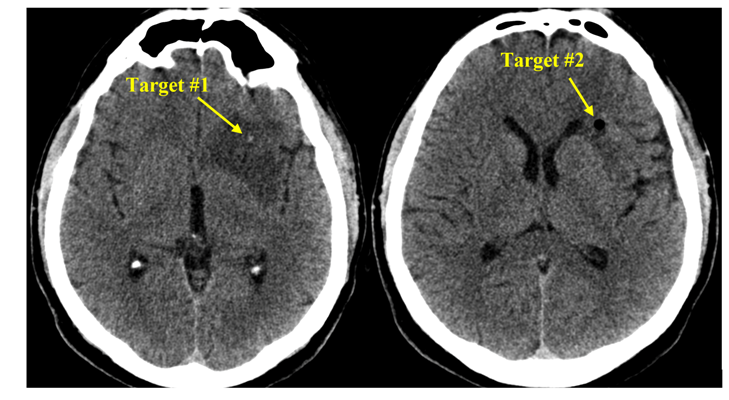

Pacientul S., a beneficiat de tehnologiile existente în volum deplin. Operația a durat 2 ore. Pacientul și-a revenit după o oră de la intervenția chirurgicală, iar peste o zi a fost externat. Pentru prelevarea biopsiei a fost aleasă o porțiune de tumoare localizată la adâncimea de 13 cm de la suprafață. Locul ales a fost țintit cu precizia de 0,2mm! Acest grad de precizie este suficient pentru toate biopsiile cerebrale, iar în anumite circumstanțe, sistemul poate fi utilizat și pentru tratamentul parkinsonismului.